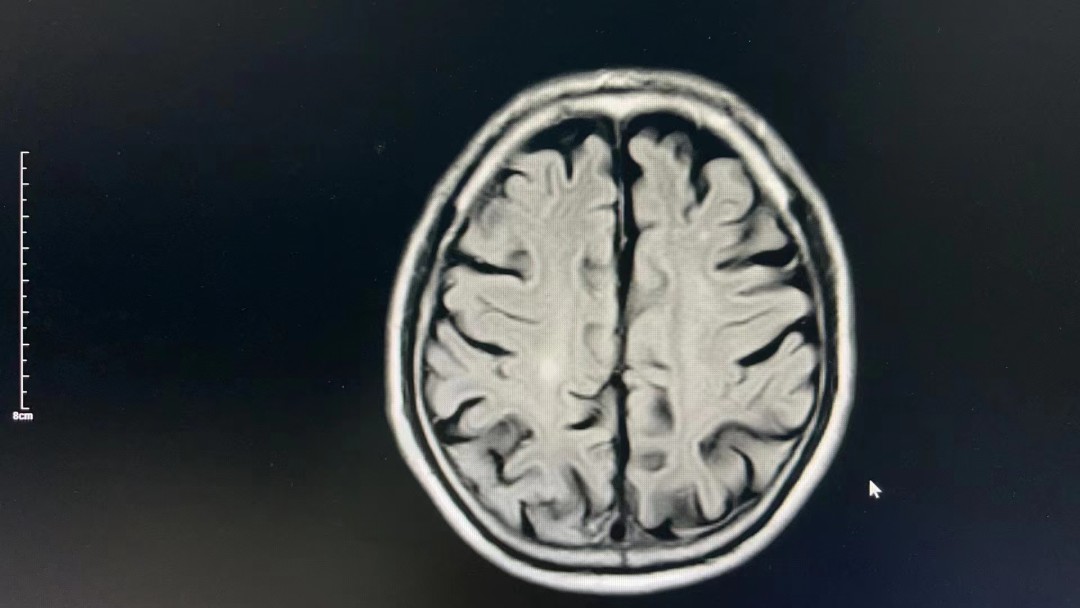

患者后續(xù)收治到西醫(yī)內(nèi)科繼續(xù)治療,完善頭顱核磁檢查后考慮:“右側(cè)大腦半球多發(fā)繼續(xù)腦梗死”,此次治療對(duì)患者遠(yuǎn)期生活質(zhì)量獲益較大,減少致殘率,家屬表示很感謝!